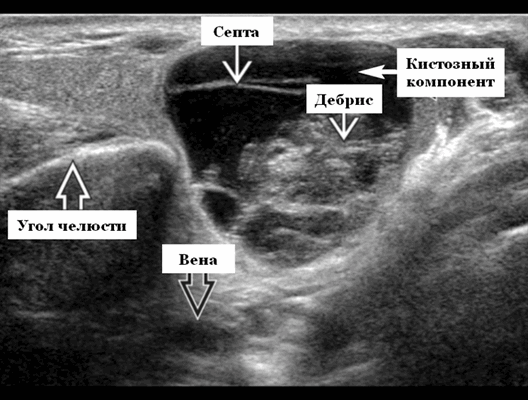

Ультразвуковая визуализация. Общие особенности. Лучший диагностический признак на УЗИ слюнной железы - резко окаймленные, гетерогенные образования околоушного хвоста ± кистозные компоненты. Расположение. Интрапаротидное, чаще, чем периаротидое или верхние шейные лимфатическое узлы. Чаще всего в пределах околоушного хвоста поверхностно от угла нижней челюсти

Результаты ультразвукового исследования слюнных желез

- Серошкальное УЗИ дает специфичность 91%, точность 89%. Большая опухоль Вартина клинически очевидна. При ультразвуковом исследовании четко выраженная гипоэхогенная некальцинированная опухоль в верхушке поверхностной доли околоушной железы. Гетерогенная внутренняя архитектура с кистозными и солидными компонентами. Мультисептированное кистозное поражение с толстыми стенками и детритом ± заднее усиление. Имеет тенденцию оставаться эллиптической или почковидной формы даже при больших размерах. Маленькая опухоль Вартина: случайная находка. Небольшая, эллиптическая, плотная почковидная масса в известном месте внутрипаротидного лимфатического узла. Гетерогенная архитектура и эхогенные ворота. Имитирует внешний вид лимфатического узла. Множественность поражений, односторонних или двусторонних (20%). На УЗИ нет инфильтрации кожи или подкожной ткани